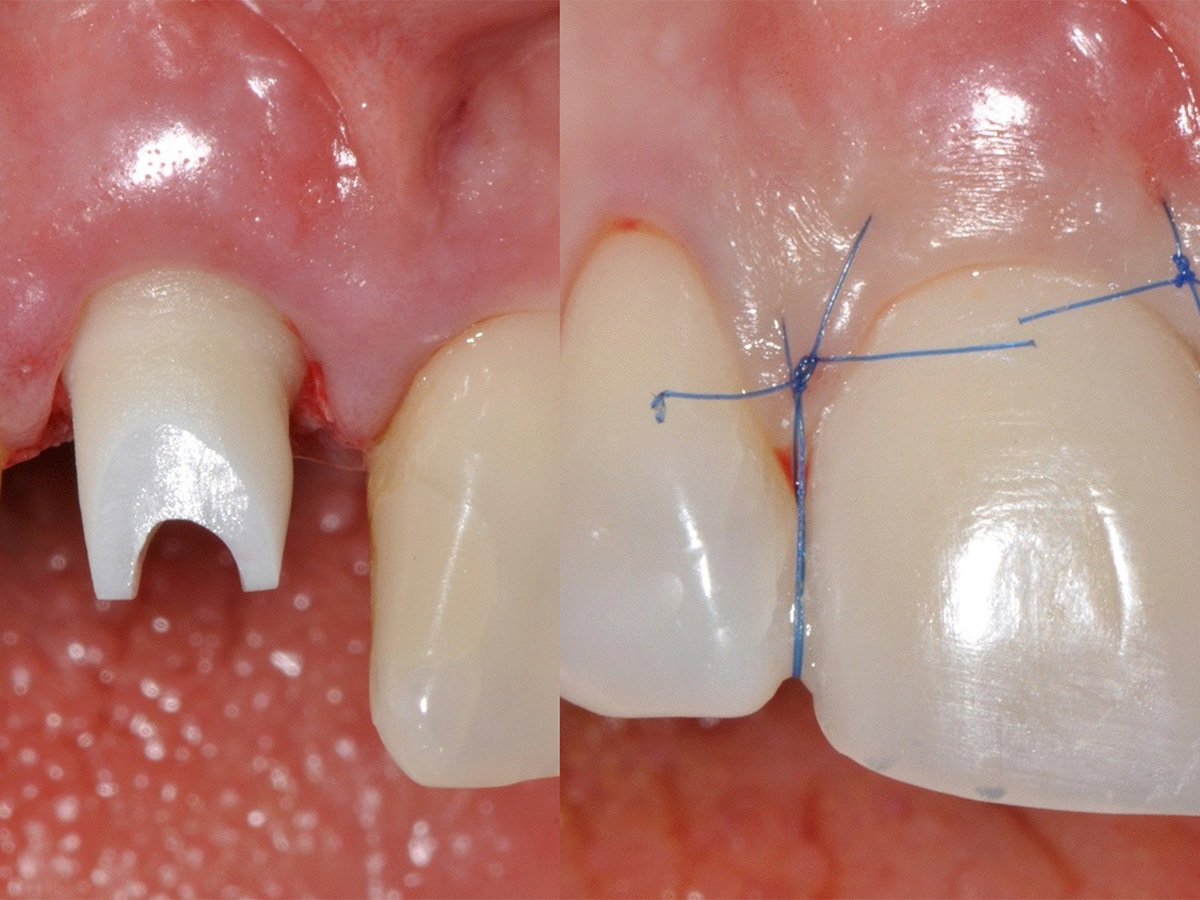

Die dreidimensionale Aufnahme verdeutlicht den nach der Extraktion des Zahns zu erwartenden Defekt. Trotz schonender Extraktion, ohne aufzuklappen, konnte das Fehlen der knöchernen bukkalen Lamelle ertastet werden. Es folgten die Präparation und die Erweiterung des Implantatbetts. Die palatinale Positionierung von Implantaten liefert in der Regel gute Ergebnisse hinsichtlich der Implantaterfolgsrate, der Stabilität des periimplantären Gewebes, des Knochenverlusts und der Patientenzufriedenheit. Das Implantat ließ sich in der idealen Position primärstabil inserieren. Zur Regeneration der knöchernen Lamelle wurde die Bone-Lamina-Technik verwendet: Es wurde ein Mukoperiostlappen mit dem Tunnelinstrument präpariert, um die porcine kortikale Knochenmatrix (Osteo- Biol Soft Cortical Lamina, Tecnoss) einbringen zu können. Die Präparation wurde minimalinvasiv und ohne Inzision durchgeführt. Die Distanz zwischen dem palatinal inserierten Implantat und der bukkal eingebrachten Bone-Lamina füllten wir mit resorbierbarem knochenregenerativem Material, der deproteinierten bovinen Knochenmatrix OsteoBiol mp3 (Tecnoss), auf. Vor dem Eingriff wurde eine Funktionsanalyse durchgeführt und Meistermodelle wurden angefertigt. Da das Implantat sehr primärstabil eingebracht werden konnte, wurde direkt nach der Operation ein Abformpfosten gesetzt und mit einem Index versehen. Dadurch kann ohne eine Abformung die exakte Implantatposition dem Zahntechniker übermittelt werden. Postoperativ wurde der Patient instruiert, dreimal täglich mit 0,2 % Chlorhexidindigluconat bis zur Nahtentfernung zu spülen. Zusätzlich wurden für drei Tage Ibuprofen 600 mg, Amoxicillin und Clavulansäure verschrieben.

Der Zahntechniker übertrug die Implantatposition auf das Meistermodell und fertigte am selben Tag das definitive Abutment mit dem idealen Emergenzprofil und eine provisorische Krone an. So konnte der Patient direkt mit dem definitiven Abutment versorgt werden. Nach einer Einheilphase von drei Monaten wurde zur Stabilität der peri - implantären Weichgewebsarchitektur das Gewebe verdickt. Eine sehr gute Technik dafür ist die Entnahme eines entepithelialisierten Transplantats aus der Tuberregion. Dies wurde mit der Tunneltechnik eingebracht und mit Nähten fixiert. Die definitive Versorgung des Implantats erfolgte nach einer Einheilzeit von acht Wochen. Im finalen Bild lässt sich gut erkennen, dass das Volumen erhalten werden konnte.

Abbildung 3

Implantatinsertion.

Abbildung 4

Es wurde ein Mukoperiostlappen mit dem Tunnelinstrument präpariert...

Abbildung 5

... um die porcine, kortikale Knochenmatrix (OsteoBiol Soft Cortical Lamina, Tecnoss) einbringen zu können.

Abbildung 6

Da das Implantat sehr primärstabil eingebracht werden konnte, wurde direkt nach der Operation ein Abformpfosten gesetzt und mit einem Index versehen.

Abbildung

Definitives Abutment.